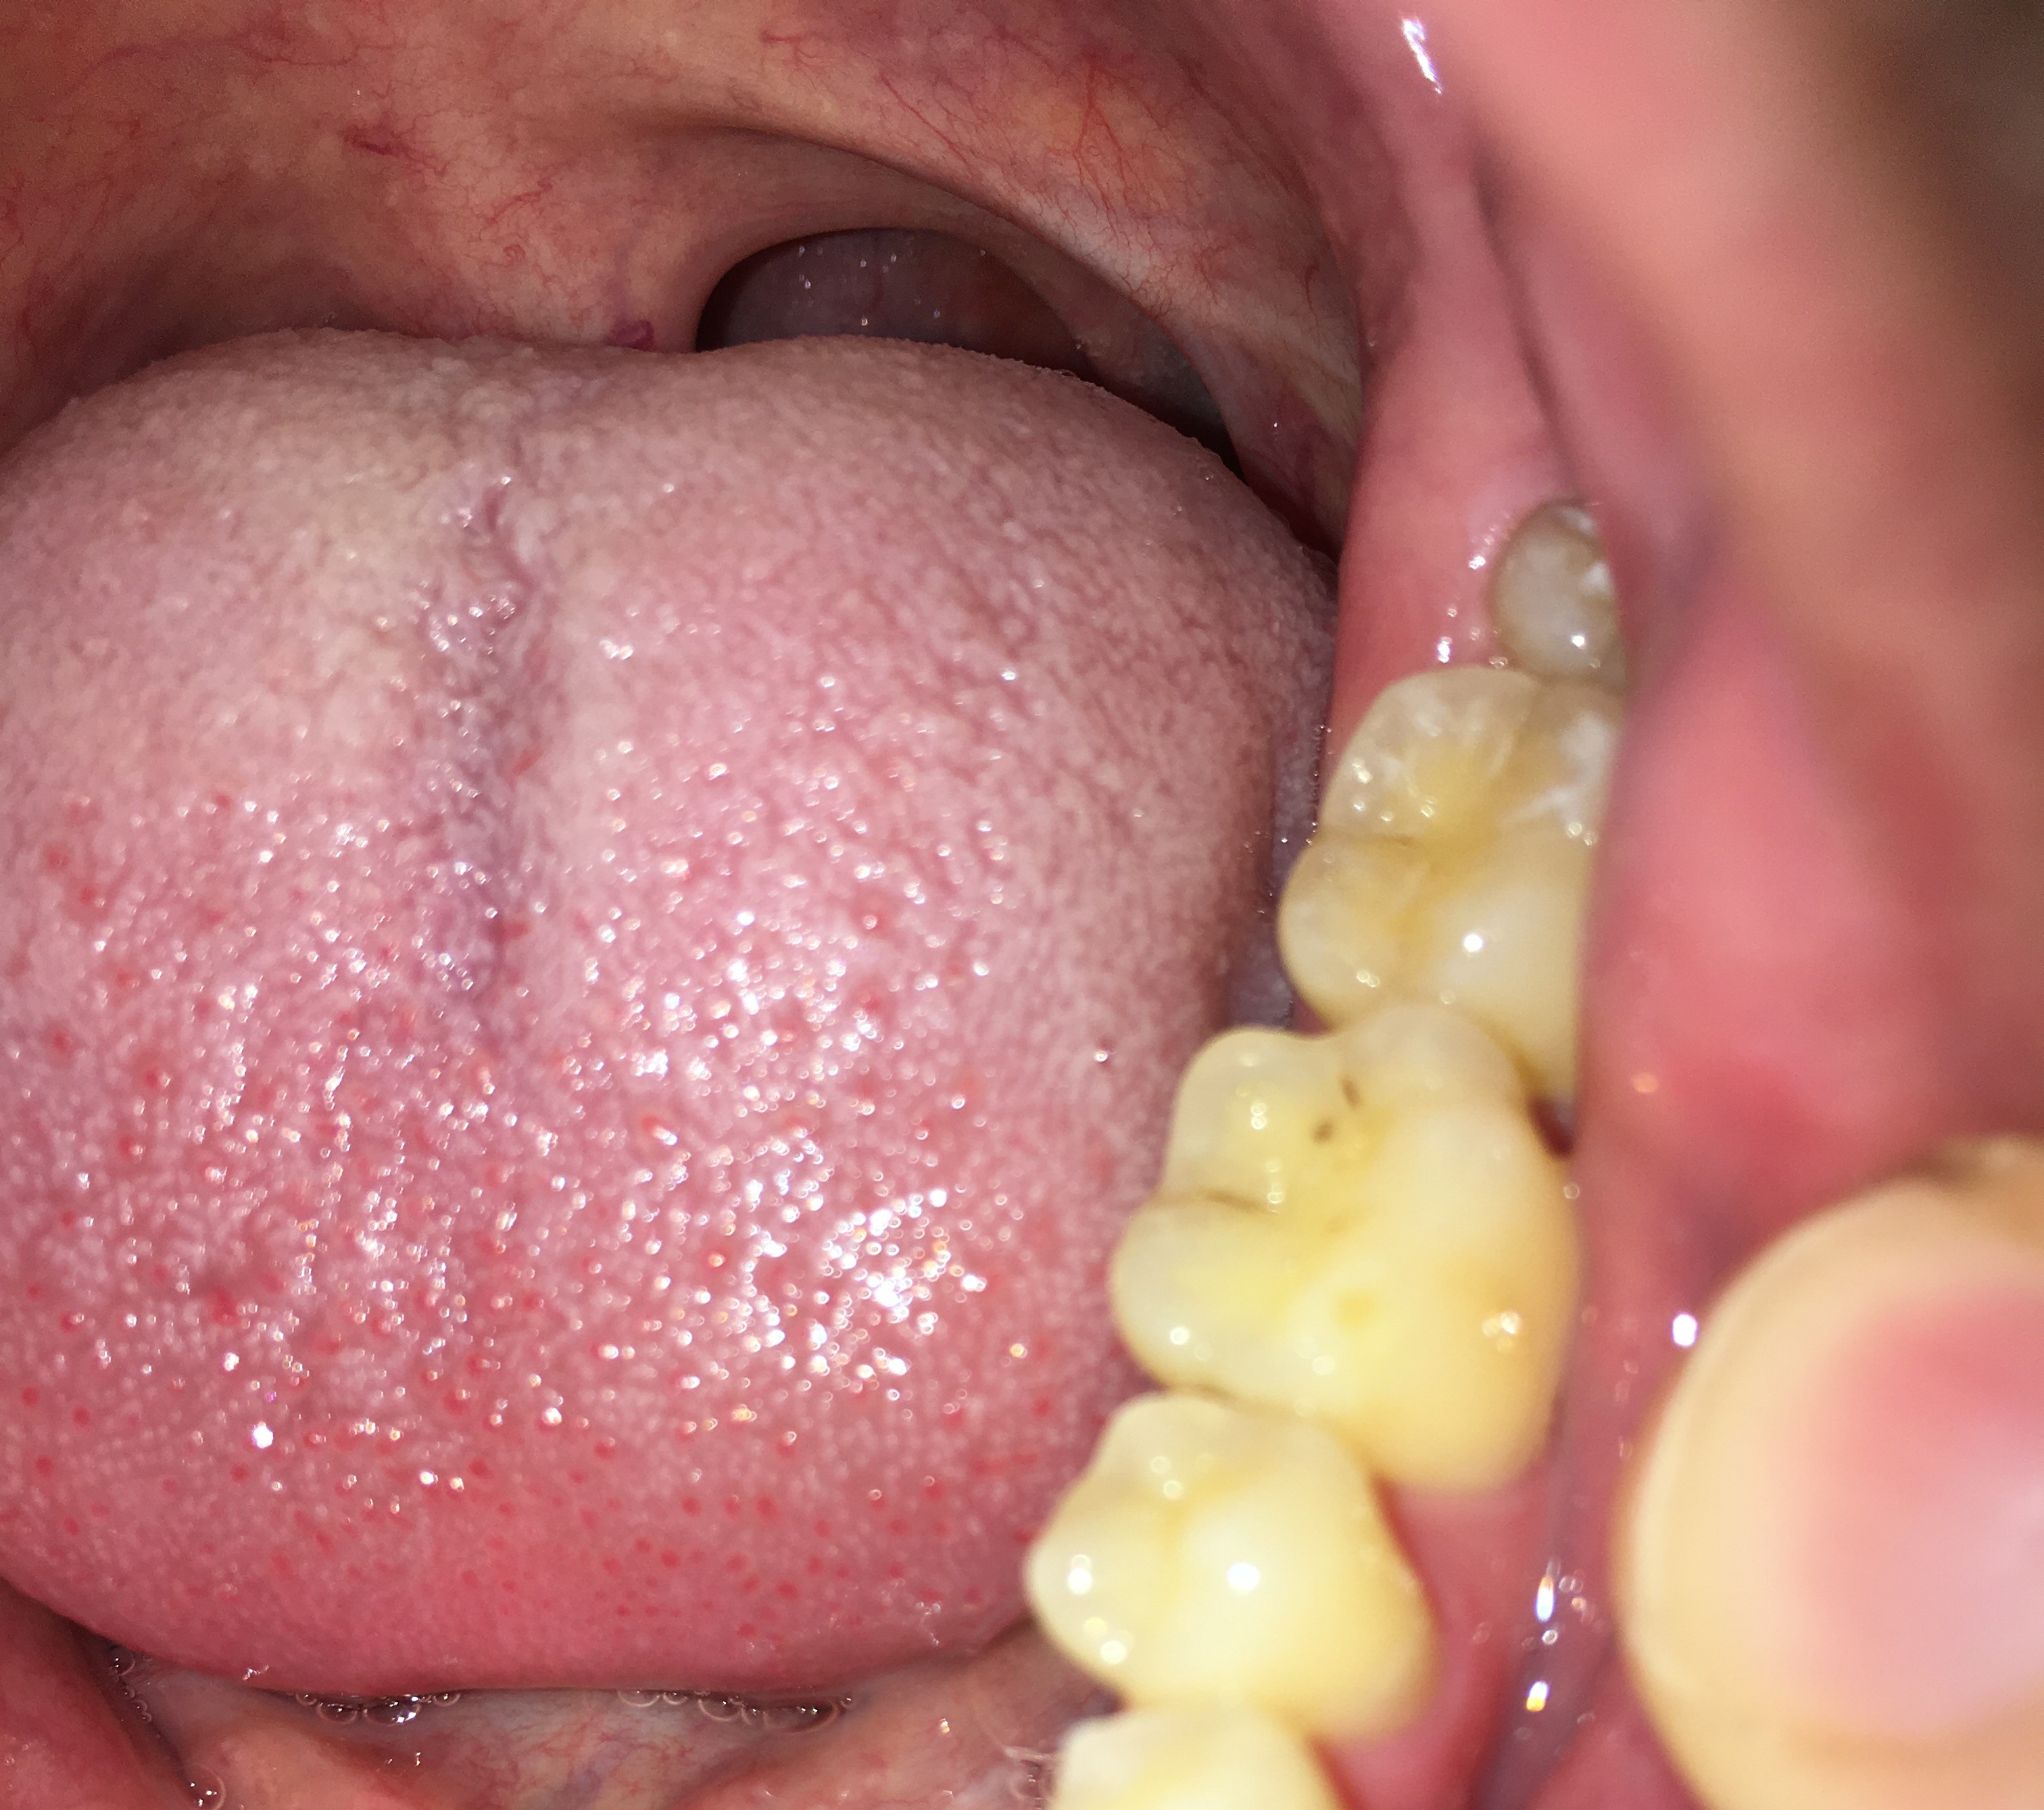

Ik zie dat de randen van mijn tanden en kiezen best doorzichtig zijn en las dat dit tanderosie kan zijn, daarnaast zie ik de dentine. Ik nuttig geen suikers of zuren dus ik begrijp niet waarom ik dit zou hebben. Daarnaast heeft de tandarts er nooit wat over gezegd. De eerste foto is van vandaag, de andere van 2015 (foto's van de boventanden). Als ik deze twee foto's vergelijk zie ik dat er geen verschil is en dat bij beide foto's evenveel doorzichtigheid en dentine te zien is.

De laatste foto is ook van vandaag, van de ondertanden. Moet ik me zorgen maken?

Nee, ook niet echt in mijn tienerjaren. Mijn tandarts of mondhygiënist hebben er nooit wat over gezegd, maar op andere (buitenlandse) online forums wordt door tandartsen gezegd dat er inderdaad sprake is van erosie. Ben een beetje geschrokken omdat ik geen frisdranken of koolzuurhoudende dranken nuttig. Als u zo naar de foto's kijkt, met name de eerste en tweede foto waar 10 jaar tussen zit. Zou je dan kunnen zeggen dat het gelijk is gebleven?

De tweede foto v d bovenkaak is niet duidelijk en voor de onderkaak is geen tweede vergelijking. Hoe is de PH v uw speeksel, wat eet u ...v zoveel factoren afhankelijk. Enige wat ik zie is dat u vrij doorzichtige tanden/kiezen heeft Dat hoeft niet negatief te zijn.

De tweede foto is inderdaad niet heel scherp, maar als je goed kijkt zie je dezelfde doorzichtigheid (heb een foto met pijltjes toegevoegd). Ik eet best gezond en mondhygiëne is ook best goed, ik vermijd suikers en drink voornamelijk water. Geen idee wat de PH is helaas, vind het ook apart dat mijn tandarts er nooit wat over heeft gezegd.

Hierbij 3 foto's van mijn onderkaak. De eerste foto is van mijn linker onderkaak van 2017, de tweede foto is van mijn rechter onderkaak van 2017 en de laatste foto is van 2015 van mijn gehele onderkaak. De foto van 2015 is met een andere telefoon genomen, hierdoor is de kleur en belichting wat anders, echter zie ik bij alle drie de foto's en de foto van 2025 de zelfde hoeveelheid doorzichtigheid.